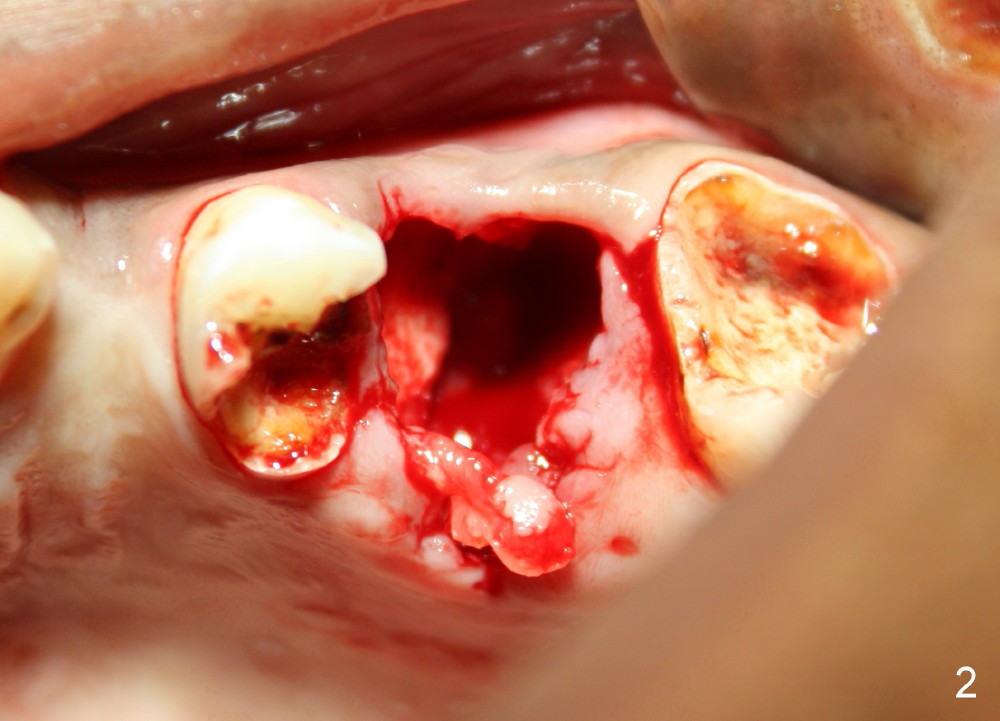

Rishawn, 23 years old, has had severe caries. The tooth #14 is unsalvageable (Fig.1). Due to finance, immediate implant is not considered. Upon extraction, there is no septum, probably resulting from infection (Fig.2). Six days later, dry socket develops with excruciating pain (Fig.3 *: yellowish and grayish exudates in the socket). The chance of dry socket would have dropped if the immediate implant were placed.